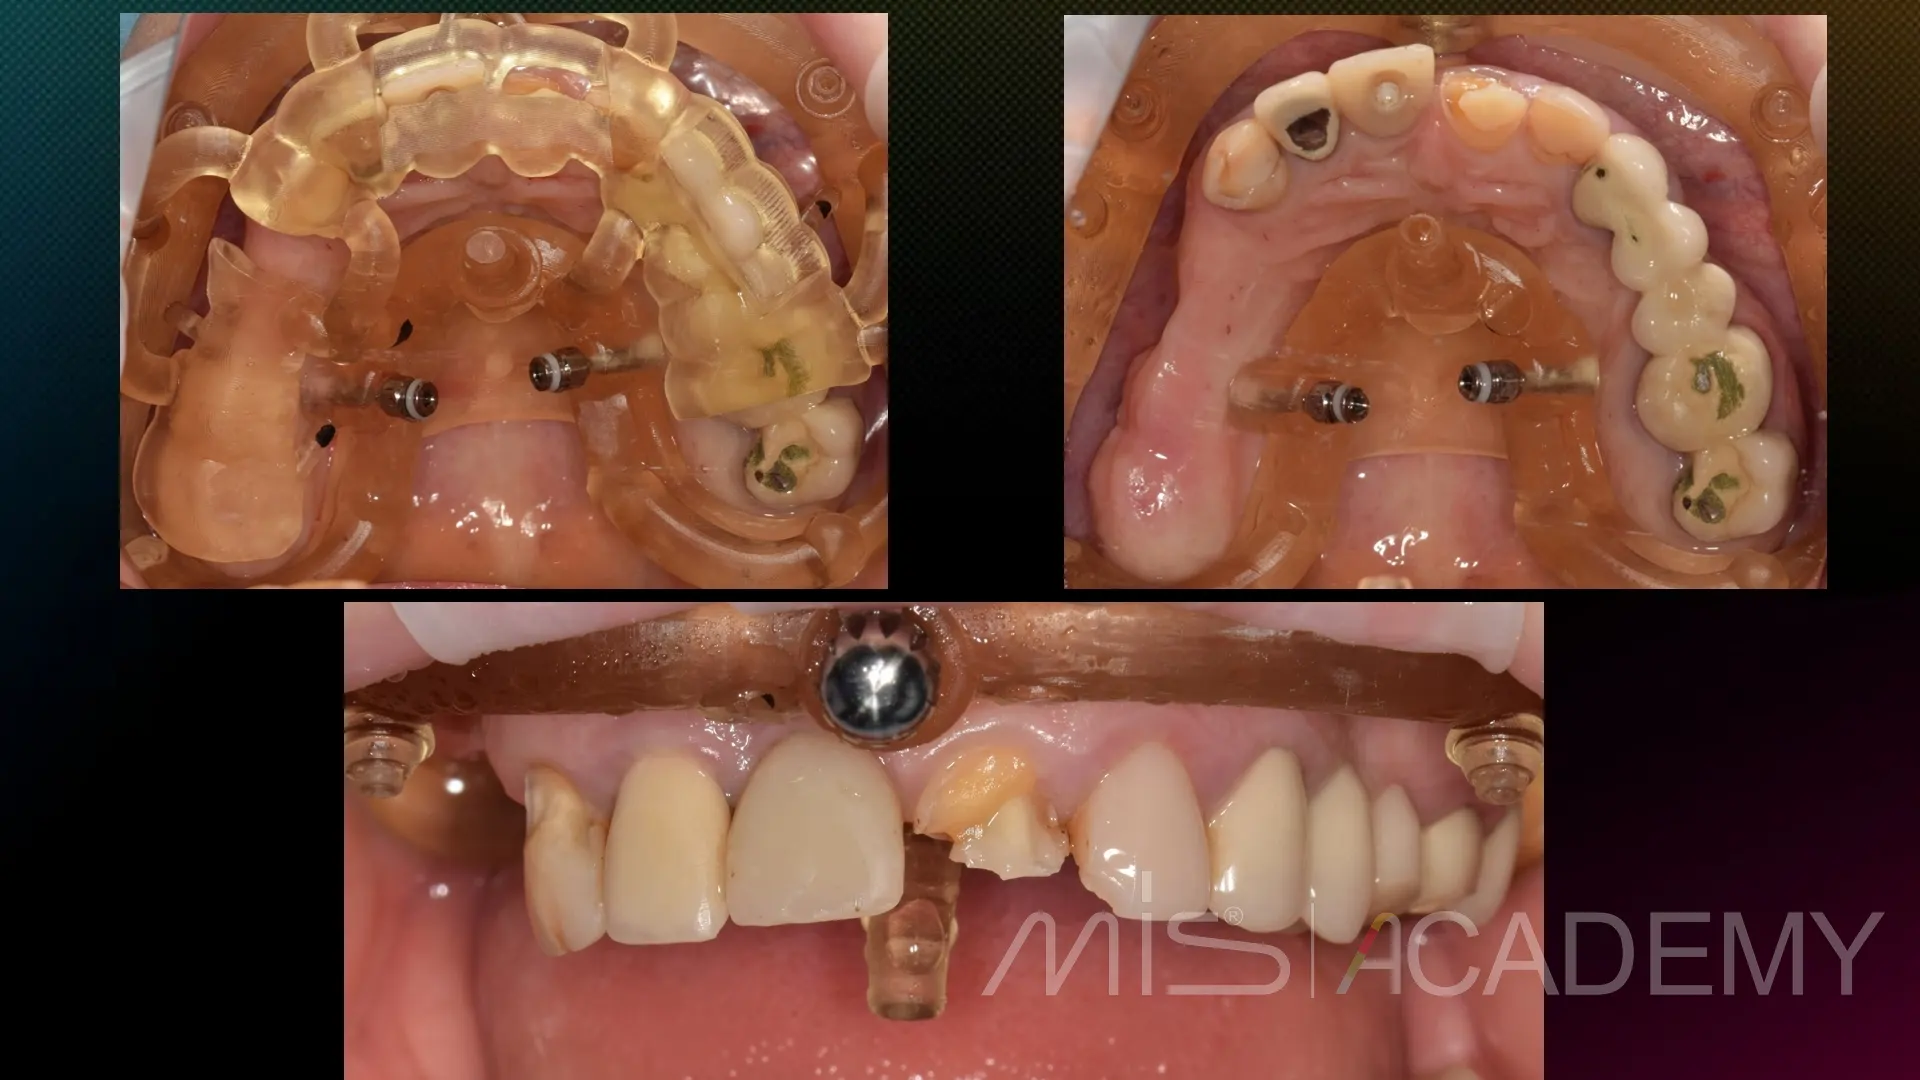

Промежуточный этап тотальной реабилитации.

2. MockUp на нижние передние зубы, новые временные протезы на имплантаты, установленные 7 лет назад, на новой высоте прикуса.

3. Удаление зубов на в/ч, установка 6 имплантатов MIS C1 по навигационному шаблону, мультиюнит абатменты, CONNECT абатменты в переднем отделе, в лунки — bio-oss, стимул-осс, пластика десны.

4. Временный протез в день операции.